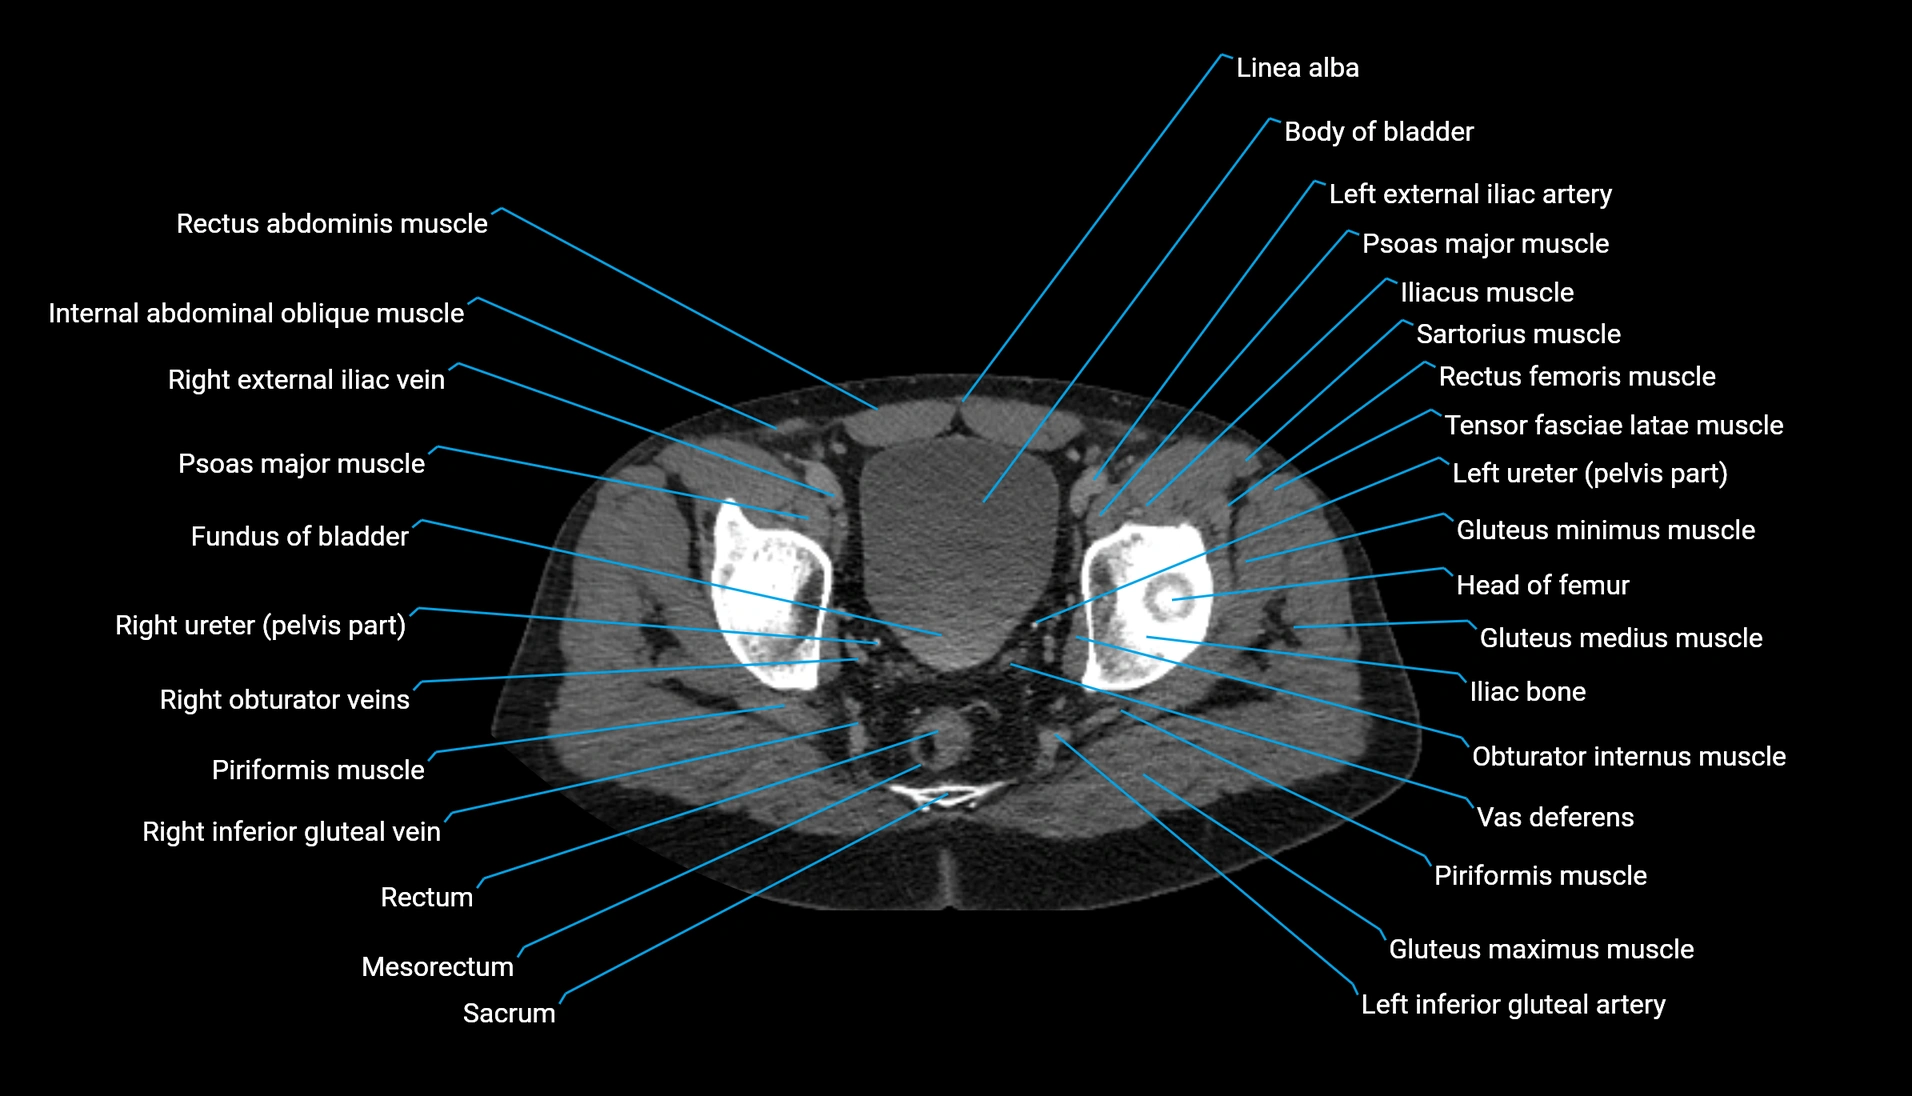

CT Appearance

Non-contrast CT:

-

Demonstrates cortical bone of acetabular rim in excellent detail

Detects fractures, dysplasia, retroversion, or bony overcoverage (pincer impingement)

3D reconstructions used in preoperative hip surgery planning

CT VRT 3D image

CT image